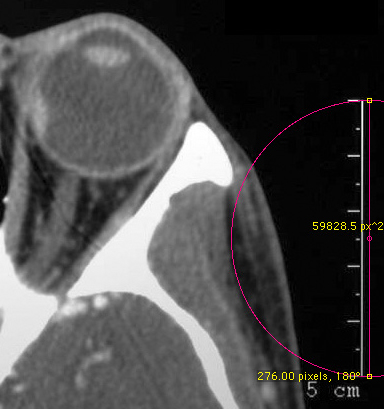

buttons The more common PC file formats such as jpg, pict, gif, tiff etc... that you might obtain using a film scanner require manual calibration. The original films usually have a calibration ruler included in the image. Click the Measure button in Madena's control panel to display the diametric measurement tool. (You can control-click on this button for additional tools). Drag the tool's yellow control markers over the ruler in the image as illustrated below.

Click the Calibrate button in Madena's control panel (just below the Measure button) to display the calibration dialog. Enter the ruler distance (5.0 cm in this example) and then click OK to exit the dialog.